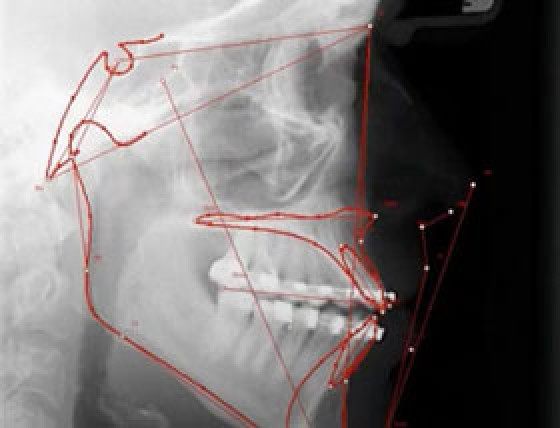

Mit der Fernröntgen-Analyse in der digitalen Kieferorthopädie behalten Sie Wachstumsverläufe und Behandlungsfortschritte jederzeit präzise im Blick.

- grafische Überlagerung von Durchzeichnungen in beliebigen Ebenen

- tabellarische Gegenüberstellung von Anfangs-, Zwischen- und Endbefund sowie Überlagerung von Bild und Tracing

- Analysevorlagen nach Bergen, Bjork, Hasund, Jarabak, McNamara, McGann, Rakosi, Ricketts, Sampermans, Segner, Steiner, Sato, Slavicek, Tweed, Wingberg u. v. m.

Mit den Visual Treatment Objectives (V.T.O.) simulieren Sie Behandlungsziele und machen Therapieergebnisse schon vorab sichtbar – ein starkes Tool für die digitale Behandlungsplanung.

- Visual Treatment Objectives (V.T.O.) nach Ricketts zur Visualisierung des Behandlungsziels

- Behandlungssimulation durch Überlagerung von Foto und FRS-Durchzeichnung im Zusatzmodul simulation